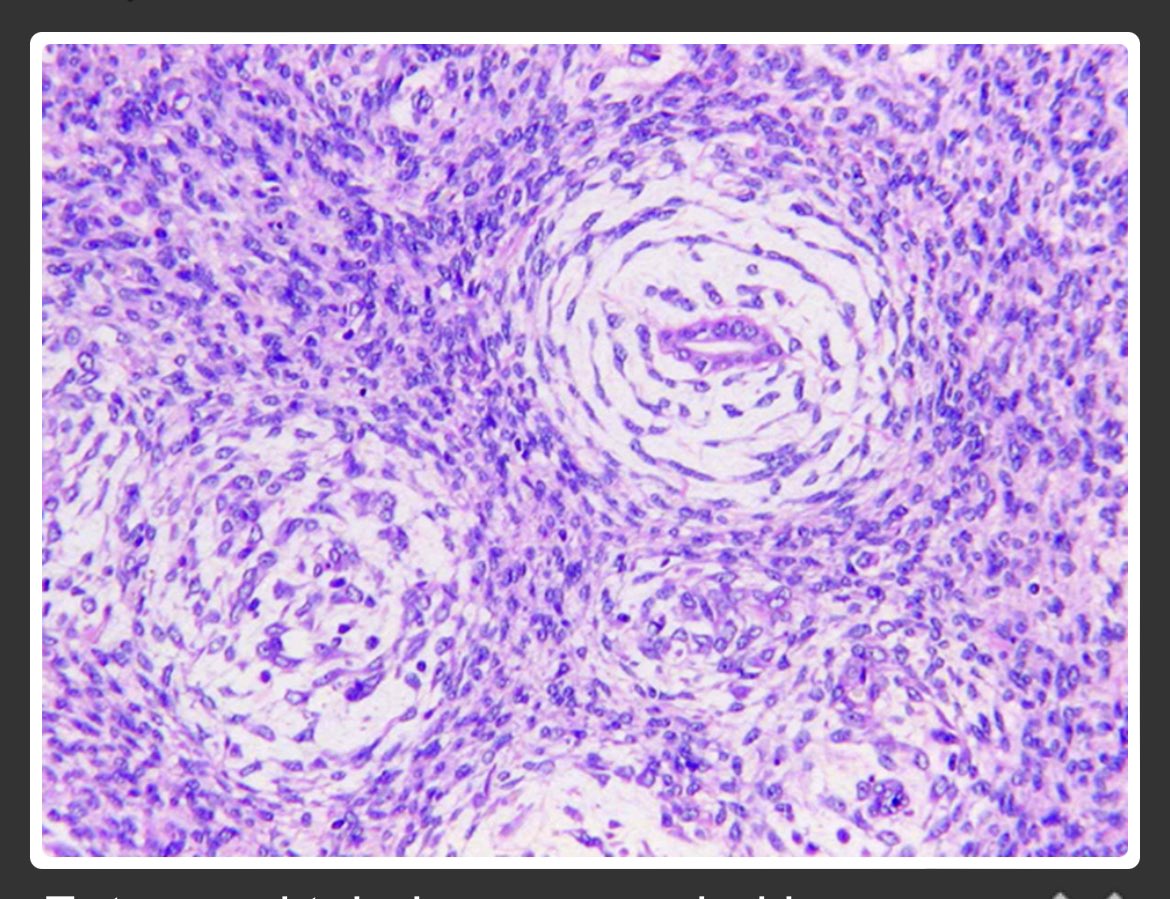

NR4A3 immunocytochemistry can be used directly on FNAC conventional smears & liquid-based cytology to reliably distinguish acinic cell carcinoma from its mimickers. This may be useful in cases where a cell block preparation is unavailable or inadequate. acsjournals.onlinelibrary.wiley.com/doi/full/10.10…